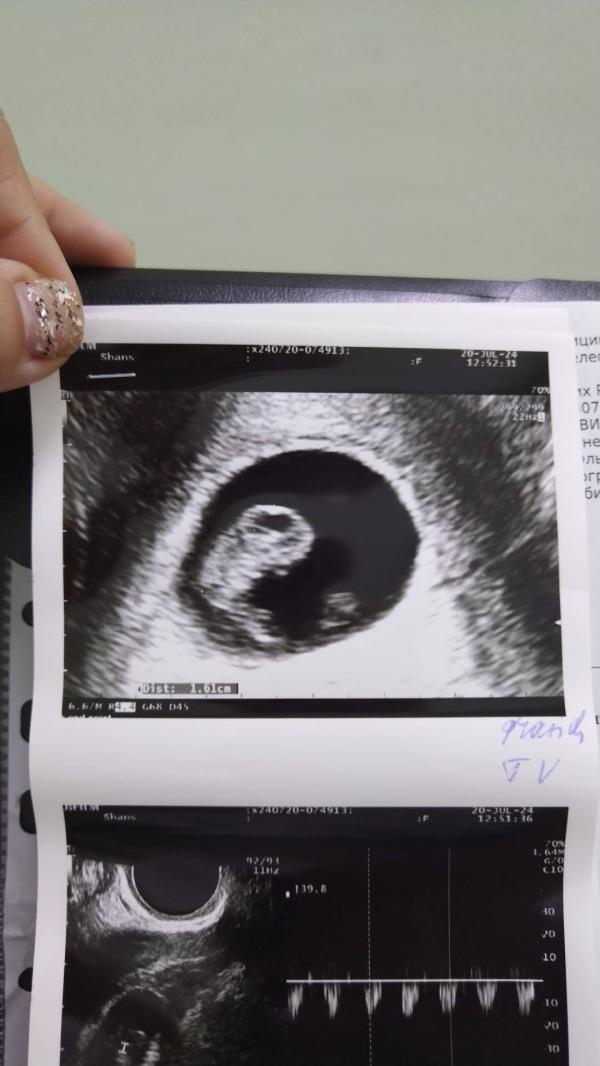

После второй попытки я опустила всю ситуацию. Мы поехали в отпуск, я взяла все необходимые средства личной гигиены с собой в ожидании месячных и уже находясь в Волгодонске у сестры в гостях поняла что у меня задержка! Делаю вечером тест... Долгожданные две полоски, утром еще темт, так де две, делаю цифровой показывает 3+. С волнением идем с мужем на узи что бы избежать повторной внематочной и слышим заветные слова. Все хорошо, эмбрион на месте. Девочки, ни когда не сдавайтесь, верьте в чудо, верьте в себя и своего партнера. Я желаю всем огромной удачи и исполнения самой заветной мечты.